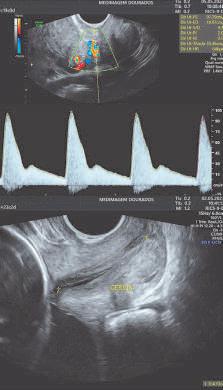

Com a gravidez confirmada, o pré-natal é realizado em consultas, onde além da avaliação clínica, o obstetra solicita exames para avaliar as condições da mãe e fazer a triagem de algumas doenças, para o melhor manejo da gestação. Os exames de imagem, cujo principal representante é a ULTRASSONOGRAFIA, fornecem imagens de órgãos e estruturas relacionadas ao ciclo gravídico, sem quaisquer efeitos adversos a mãe e ao bebê.

1 - Exame ecográfico inicial - realizado em período próximo a 8ª semana de atraso menstrual, via endovaginal, afim de confirmar se os eventos iniciais de formação ocorreram dentro dos padrões esperados (número de fetos, idade gestacional, batimento cardíaco fetal, posição da placenta, etc.).

2 - Exame morfológico do 1º trimestre / obstétrico com translucência nucal, com Doppler materno e fetal - feito entre 11 semanas e 13 semanas e 6 dias para avaliar a morfologia do bebê, placenta, líquido amniótico e colo uterino. Existem alguns sinais (marcadores) no feto, que podem ser mais frequentes em bebês com alguma anormalidade estrutural e/ou genética, possibilitando quantificar riscos de doenças que podem acometer a mãe e o bebê (risco de doenças genéticas, risco de parto prematuro e risco de pré-eclâmpsia).

Nos casos com triagem positiva (presença do sinal) existem protocolos assistenciais específicos com uso de atividade terapêutica própria. Estas análises de riscos, em conjunto, são conhecidas como Classificação/Curva de Risco, que utilizam uma ferramenta específica, o software disponibilizado para médicos certificados/auditados pela FMF – Fetal Medicine Foundation, necessário para confiabilidade e reprodutibilidade dos números encontrados.

3 - Ultrassom morfológico do 2º trimestre com Doppler materno/fetal e avaliação do colo uterino - realizada preferencialmente entre a 20ª e 24ª semanas de gestação, onde é feita uma análise minuciosa da anatomia do feto, com inte-

resse em órgãos e sistemas próprios da vida fetal, avaliação da circulação sanguínea (do útero, feto e placenta) por meio do Doppler, além da medida do colo uterino como triagem de parto prematuro.

4 - Ultrassom obstétrico com Doppler materno e fetal - realizado a partir do segundo trimestre para acompanhamento do crescimento fetal e circulação materno fetal (vitalidade fetal).

5 - Ultrassom obstétrico 3D, 4D e 5D - feita preferencialmente no segundo/terceiro trimestre, a partir da 26ª semana de gestação, cuja tecnologia permite a formação de imagens realísticas do feto.

6 - O Perfil Biofísico Fetal – executado no segundo e terceiro trimestre, a partir da 24/26ª semana de gestação, sendo recomendado para avaliar a vitalidade (bem-estar) fetal.

7 - Procedimentos invasivos fetal guiados por ultrassom - realizados para coleta de material fetal e/ou placentário em condições de acometimento fetal (como estudo genético do feto, coleta de sangue fetal, drenagem de líquido ou coleções no feto, etc.).

A ultrassonografia mudou a assistência de todo ciclo reprodutivo, com acurácia e sensibilidade na detecção de doenças e/ou condições adversas que necessitem de intervenções terapêuticas específicas. O EXAME é operador dependente, cujos resultados estão diretamente relacionados à formação, ao conhecimento e expertise. Procure sempre realizar com o especialista habilitado.